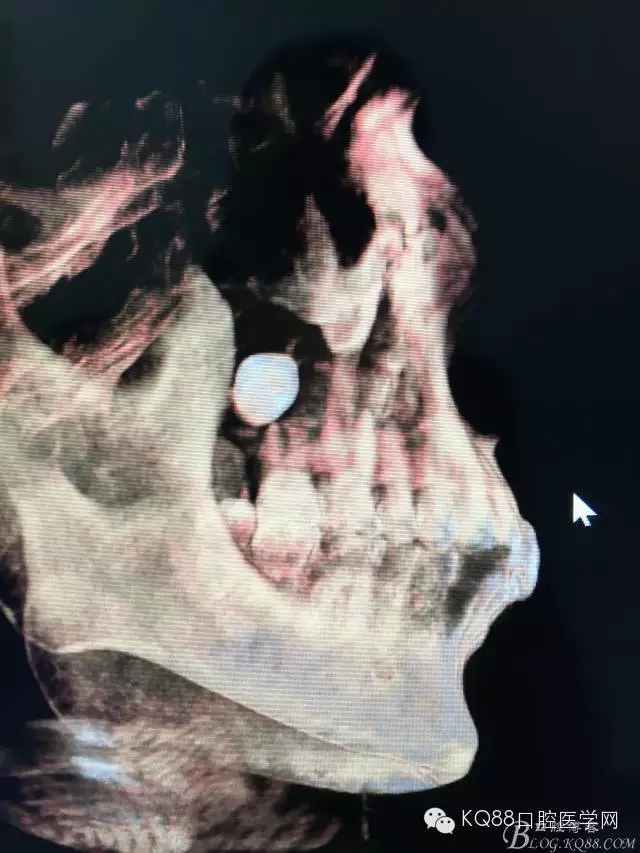

圖5. 右側三維側面觀:18位于竇腔內(nèi)。上頜竇后份的頰側骨壁完全破壞消失。